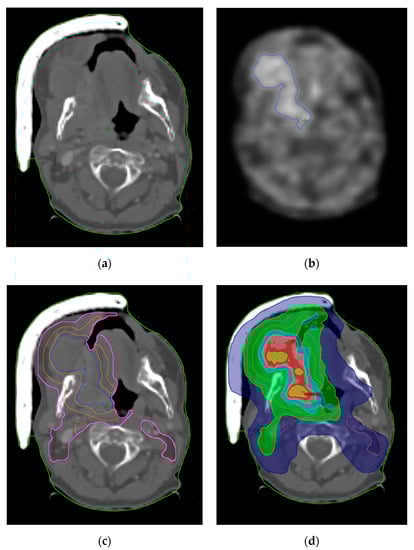

- Nishikawa, Y.; Yasuda, K.; Okamoto, S.; Ito, Y.M.; Onimaru, R.; Shiga, T.; Tsuchiya, K.; Watanabe, S.; Takeuchi, W.; Kuge, Y.; et al. Local relapse of nasopharyngeal cancer and Voxel-based analysis of FMISO uptake using PET with semiconductor detectors. Radiat. Oncol. 2017, 12, 148. [Google Scholar] [CrossRef]

- Pigorsch, S.U.; Wilkens, J.J.; Kampfer, S.; Kehl, V.; Hapfelmeier, A.; Schläger, C.; Bier, H.; Schwaiger, M.; Combs, S.E. Do selective radiation dose escalation and tumour hypoxia status impact the loco-regional tumour control after radio-chemotherapy of head & neck tumours? The ESCALOX protocol. Radiat. Oncol. 2017, 12, 45. [Google Scholar] [CrossRef] [Green Version]

- Welz, S.; Paulsen, F.; Pfannenberg, C.; Reimold, M.; Reischl, G.; Nikolaou, K.; La Fougère, C.; Alber, M.; Belka, C.; Zips, D.; et al. Dose escalation to hypoxic subvolumes in head and neck cancer: A randomized phase II study using dynamic [18F]FMISO PET/CT. Radiother. Oncol. 2022, 171, 30–36. [Google Scholar] [CrossRef]